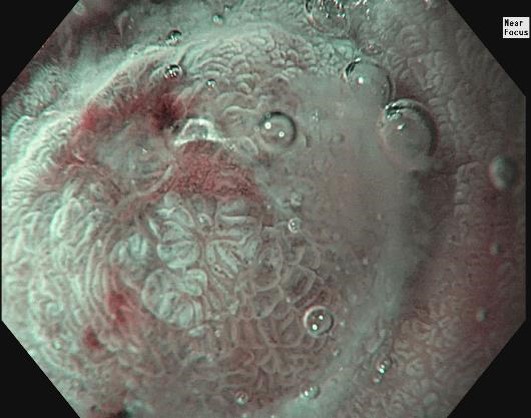

3. 1st Gastric NET (WLI, Near Focus, Under water)​

The Near Focus allow close up evaluation. The tumor can be seen beneath of the thinner part of the mucosa.